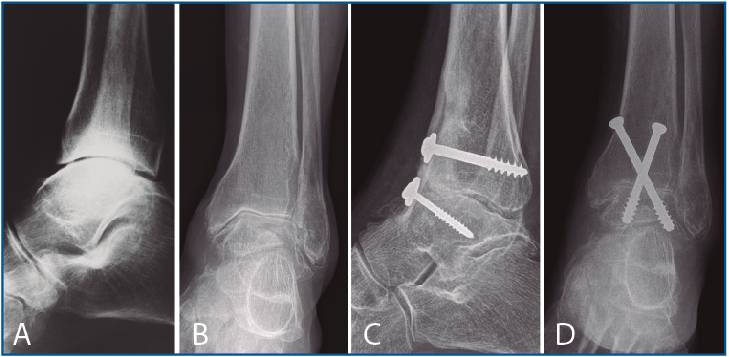

La segunda artrodesis se llevó a cabo durante el año siguiente a la primera intervención. La artrodesis fue tibioastragalina bilateral en 2 pacientes y tibiotalocalcánea (TTC) bilateral en el paciente restante. La estabilización ósea se realizó en un caso con 2 tornillos canulados Acutrak Plus® (Acumed, Hillsboro, EE. UU.) cruzados en ambos tobillos (Figura 1), en otro caso con clavo endomedular retrógrado T2 12 × 200 mm (Stryker, Schönkirchen, Alemania) en ambos tobillos (Figura 2) y en el último caso se utilizaron tornillos canulados Acutrak Plus® cruzados en el tobillo izquierdo y la técnica Putti en el tobillo derecho (Figura 3). La fijación de la artrodesis se realizó con el pie en plantígrado.

Figura 3. Caso 3. Varón de 77 años con artrosis bilateral de tobillo primaria. Radiografía lateral de tobillo derecho (A) y anteroposterior izquierdo (B) preoperatoria. Radiografía lateral de tobillo derecho que muestra una artrodesis tibioastragalina mediante técnica Putti con una consolidación parcial, asintomática, de la artrodesis y cambios degenerativos de la articulación subastragalina posterior pasados 21 meses de la intervención (C). En el tobillo izquierdo (D) se aprecia una artrodesis tibioastragalina mediante tornillos canulados cruzados del tobillo izquierdo con una consolidación parcial, asintomática, de la artrodesis al año y medio de la última intervención.